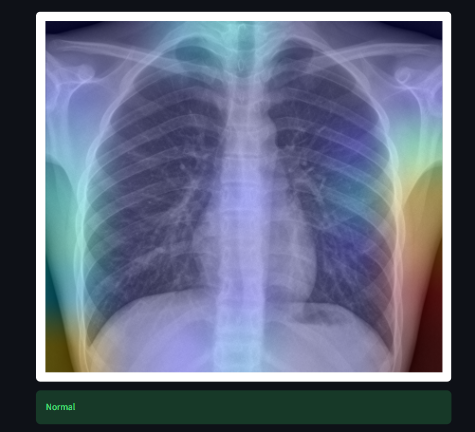

A deep learning-based medical imaging system that detects pneumonia from chest X-ray images using EfficientNet and visualizes model decisions using Grad-CAM.

The model achieves strong validation performance and provides visual explanations to improve interpretability.

• Detects Pneumonia vs Normal from chest X-rays

• Explainable AI with Grad-CAM